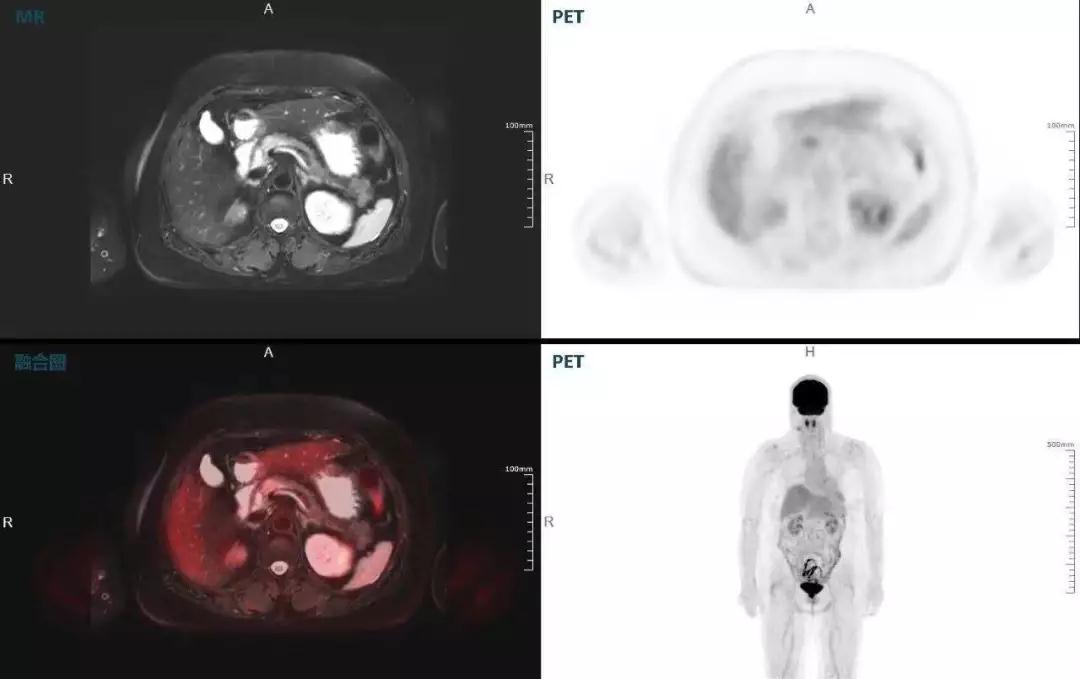

中山醫(yī)院核醫(yī)學(xué)科在臨床實(shí)踐中發(fā)現(xiàn),基于聯(lián)影“時空一體”超清TOF PET/MR,不僅解剖信息和代謝信息能夠完美融合呈現(xiàn),同時精細(xì)展示局部病灶與周圍組織的復(fù)雜關(guān)系,并能全盤檢測病灶的全身轉(zhuǎn)移,為醫(yī)生臨床診斷提供更豐富信息。

(胰腺腫瘤,MR顯示胰腺體部信號異常,PET顯示稍高攝取,結(jié)構(gòu)改變和功能異常提示胰腺M(fèi)T可能大。)